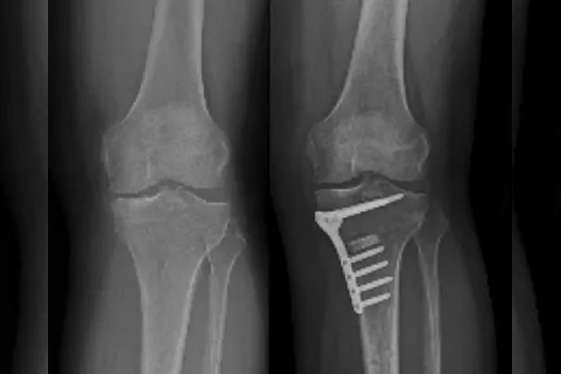

High Tibial Osteotomy (HTO)

Certain cases of knee arthritis can be successfully managed by performing HTO surgery which works by changing the alignment of the leg thus avoiding knee replacement